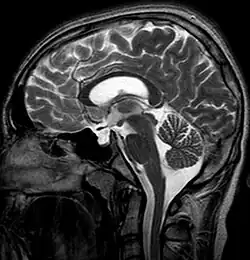

В современных реалиях магнитно-резонансная томография (МРТ) является безопасным и высокочувствительным методом визуализации хиазмально-селлярной области[22][23][24]. Данный метод позволяет проводить исследования в любой плоскости тонкими срезами в 1—1,5 мм, обладает высоким тканевым контрастом, отсутствием артефактов от костных структур черепа.

Для «пустого турецкого седла» характерна триада симптомов:

- наличие цереброспинальной жидкости в полости турецкого седла, о чём свидетельствуют зоны однородного низкоинтенсивного сигнала в режиме T1w и высокоинтенсивного сигнала в режиме T2w, гипофиз при этом деформирован, имеет форму серпа или полулуния толщиной до 2—4 мм, ткань его изоинтенсивна белому веществу мозга, воронка, как правило, расположена центрально;

- асимметричное пролабирование супраселлярной цистерны в полость седла, смещении воронки кпереди, кзади или латерально;

- истончение и удлинение воронки гипофиза.

Помимо основных изменений в параселлярной области МРТ позволяет выявить косвенные признаки внутричерепной гипертензии (расширение желудочков и ликворосодержащих пространств), сопутствующие этой патологии. Разные авторы приводят данные о почти 100 % чувствительности МРТ в диагностике синдрома «пустого» турецкого седла[20][22][23][33].